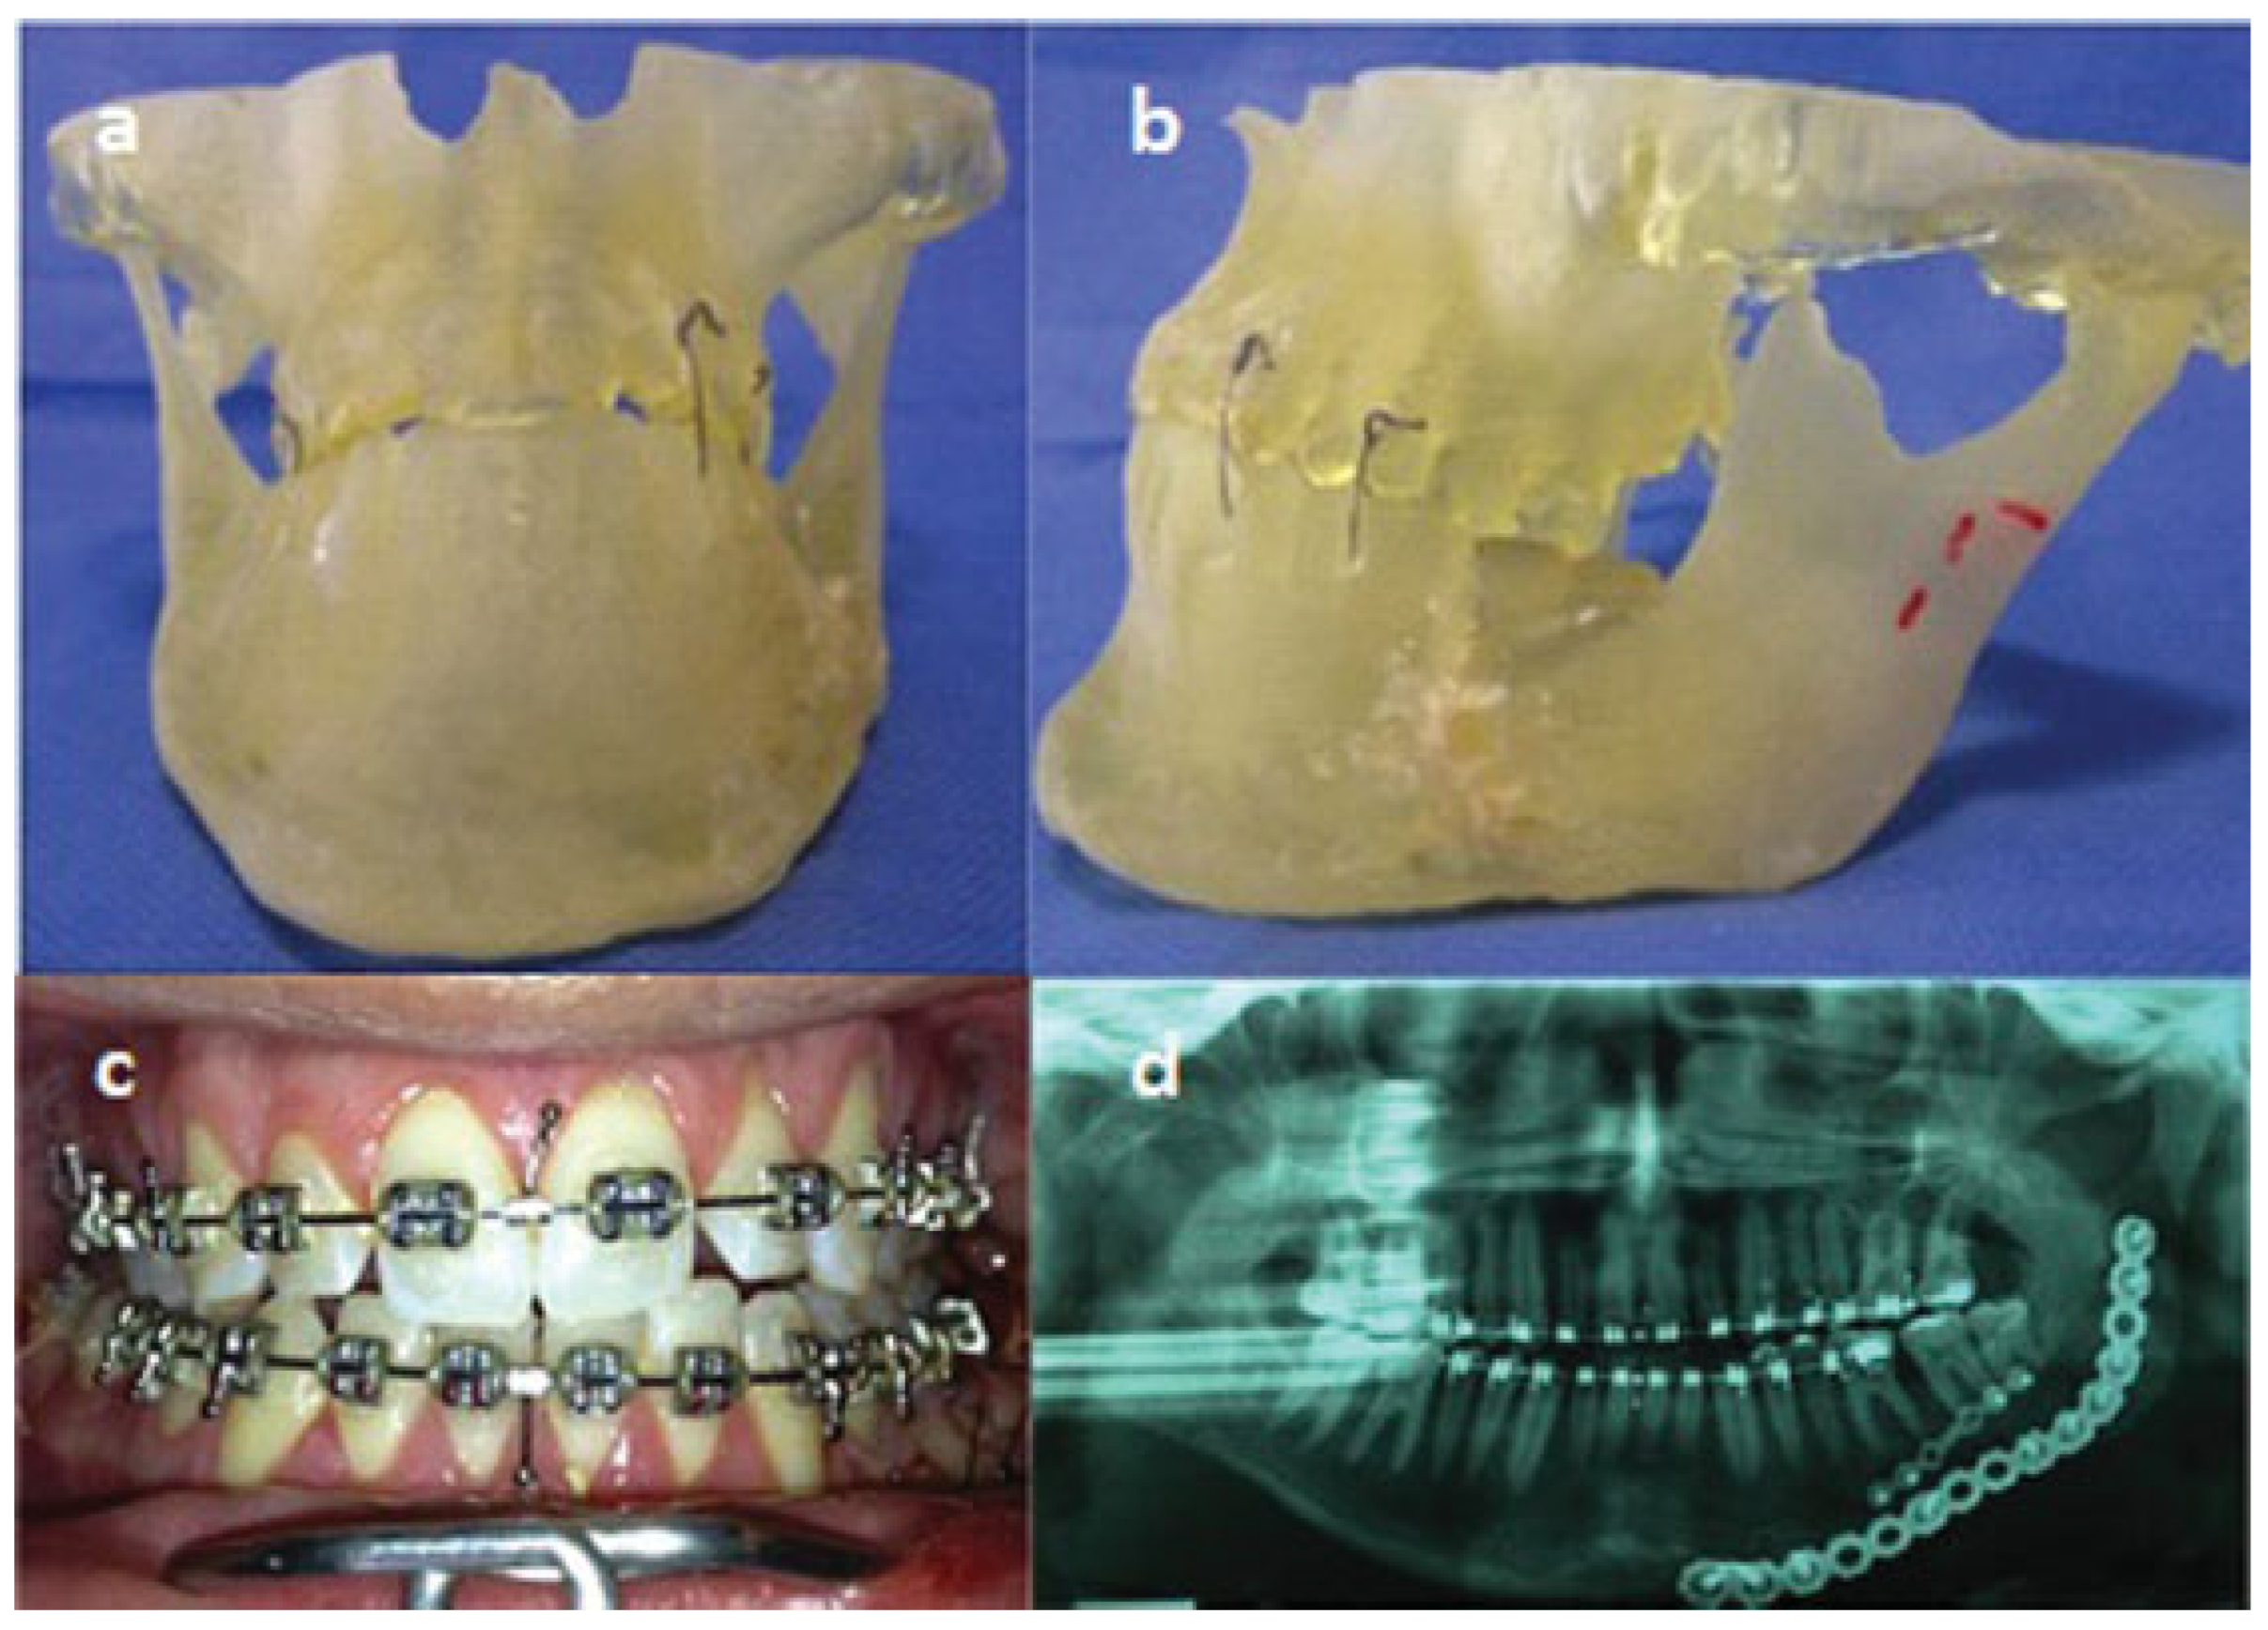

Traumatic Anterosuperior Dislocation of the Intact Mandibular Condyle into the Temporal Fossa

:Case Report